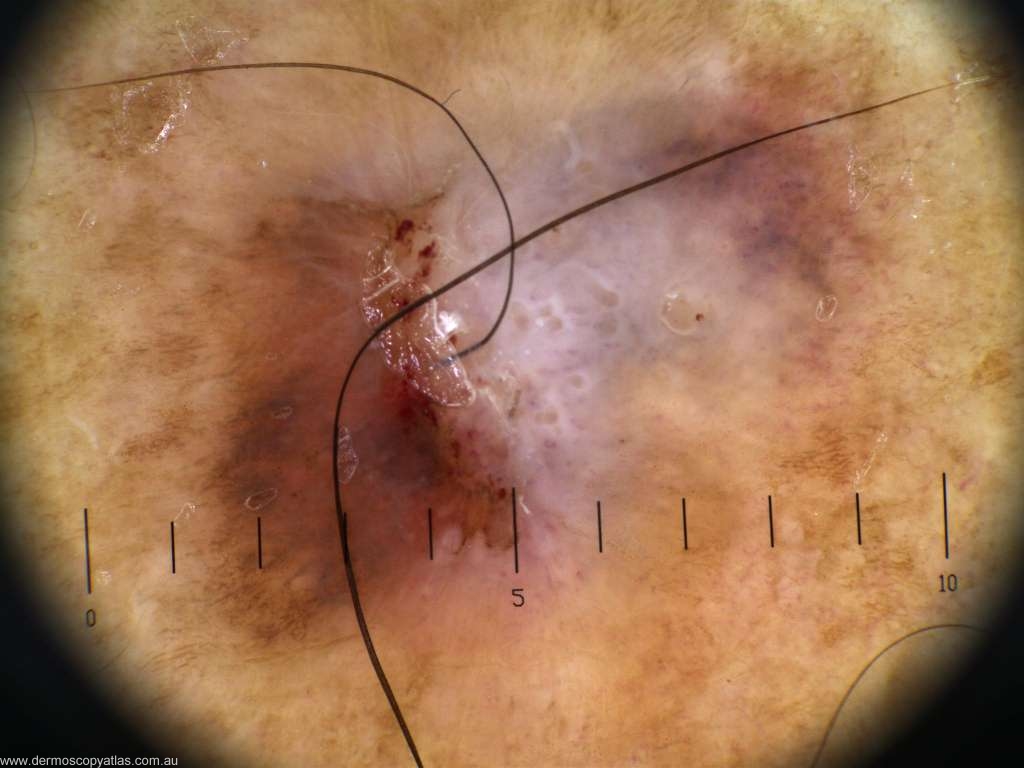

Case 3. 52 year old male auto electrician. 6 weeks of bleeding. Unsure of the appearance prior to bleeding.

Question: What is your diagnosis? Consider Junctional nevus with regression, Melanoma, Atypical Spitz, Lichen planus like keratosis or Pigmented IEC